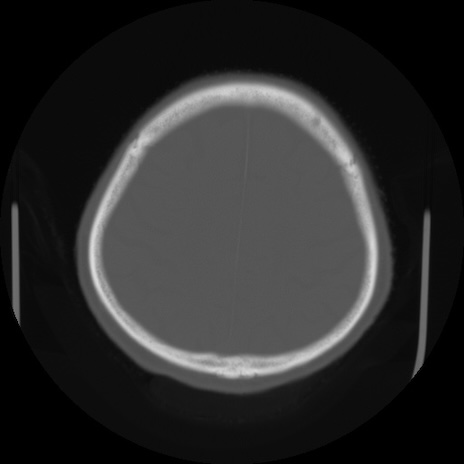

CT(冠状断像)